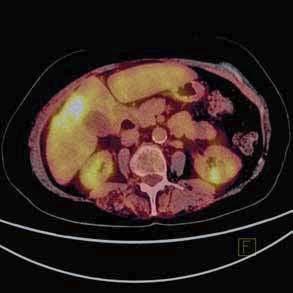

wego stopnia zaawansowania, jak i ognisk przerzutowych. Podstawowym radiofarmaceutykiem stoso-

syglukoza (18F-FDG). Zastosowanie analogu glukozy

reakcji w produkcji adenozynotrifosforanów (ATP)glukozy jest proporcjonalny do stopnia biologicznej 18F-FDG transportowana jest

sokinazy. Badanie PET jest szczególnie przydatne

zmian chorobowych stwierdzanych w innych technikach obrazowych, nowotworowych,